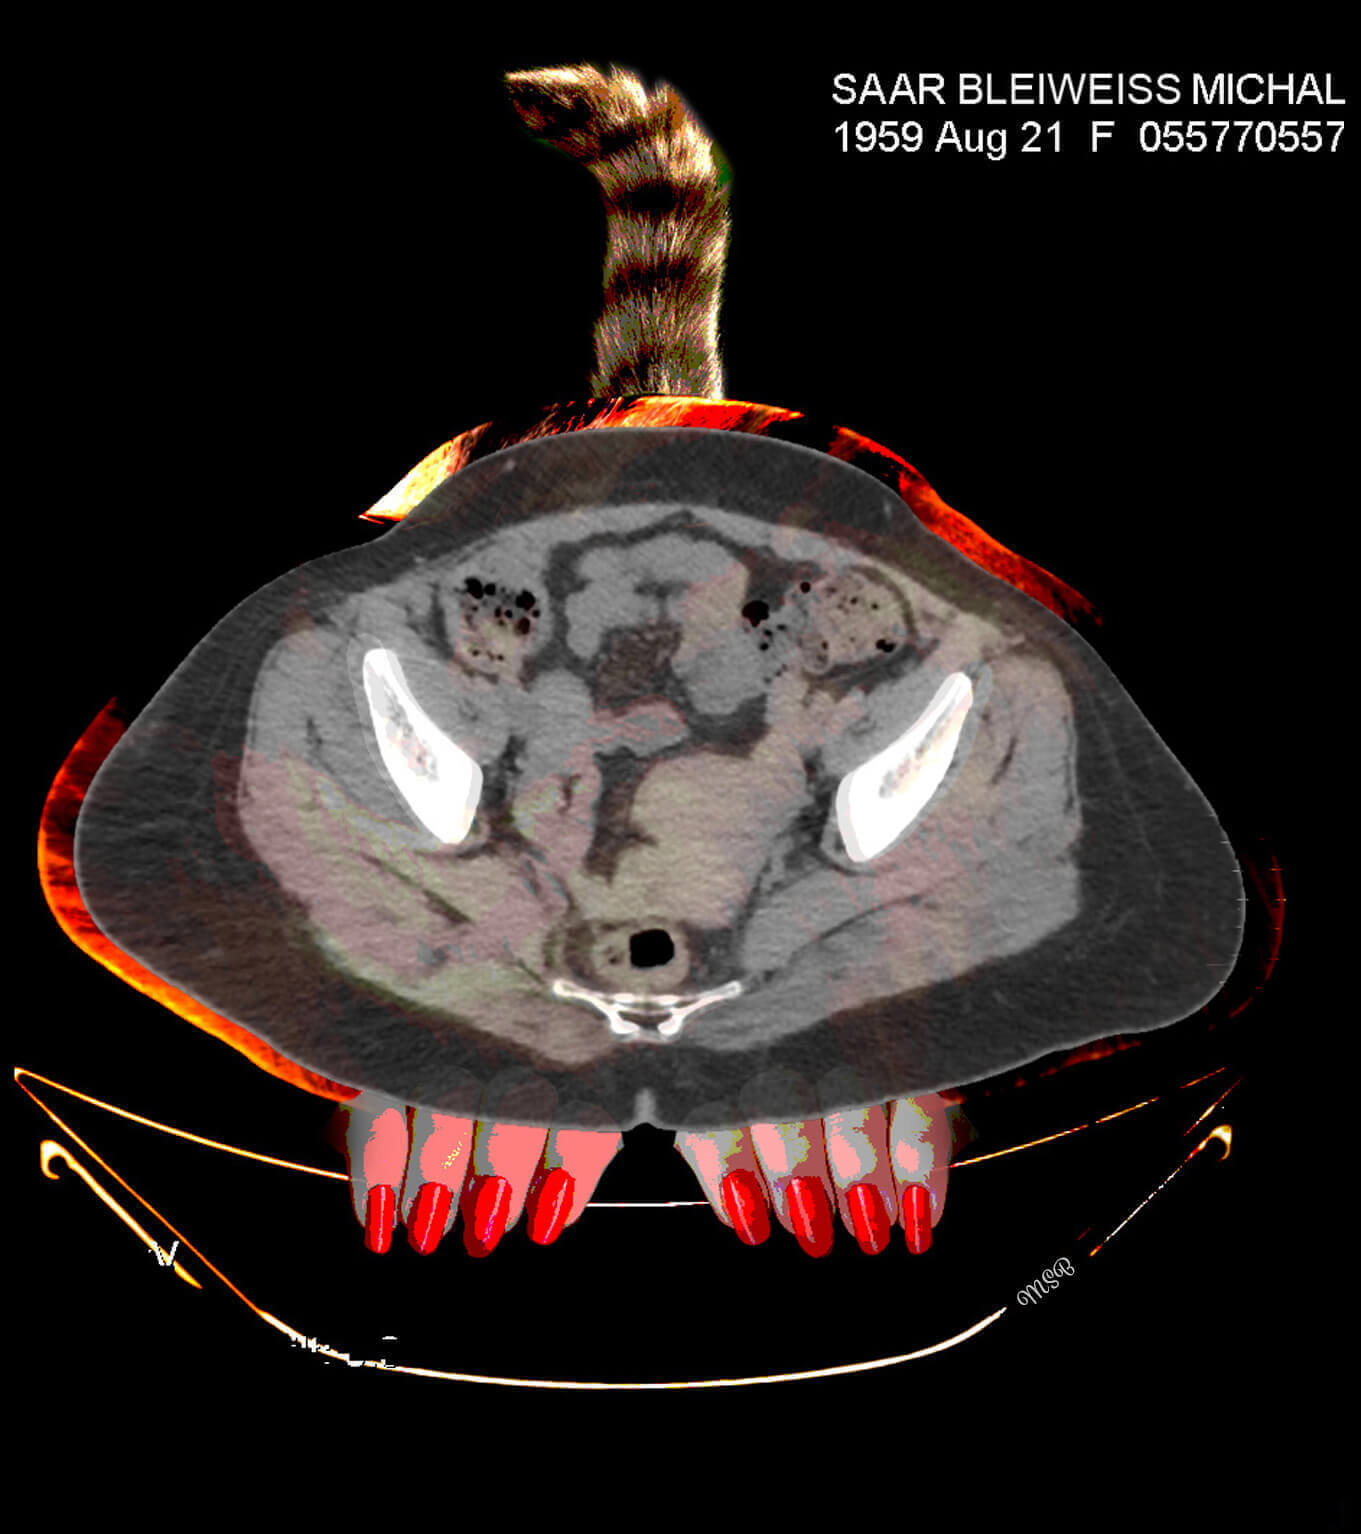

A reimagining of “self,” by Michal Saar-Bleiweiss

A few years ago, I became ill with Nephrostomy and had to undergo surgery. I was sitting with my husband, Mark, at a clinic in Ramat Aviv, Israel, in the office of a professor who specializes in CT* decoding. There, on two huge screens, for the first time I saw my body from the inside, and it was at this moment that my creative impulse arose.

The images before me were entirely in black and white, devoid of personality or character. There was no sign of the Michal that was me, and I felt a great desire and need to take these images to reinstate Michal, the person. When we returned home, I was curious about how I would feel when I looked at the images again—but this time on my computer screen. What I saw created an emotional storm within me.

This storm opened my “third eye,” enabling me to look inside myself. In my imagination I saw colors, dimensions, and expressive features, such as eyes. This was probably my way of internalizing my new reality, digesting what is going on inside me and brushing off my fears and pain. I wanted and needed to wake up each morning with a new smile and the ability to cope.

Having released the pain from the CT images, I found myself opening the next chapter in my imagination—creating digital collages.